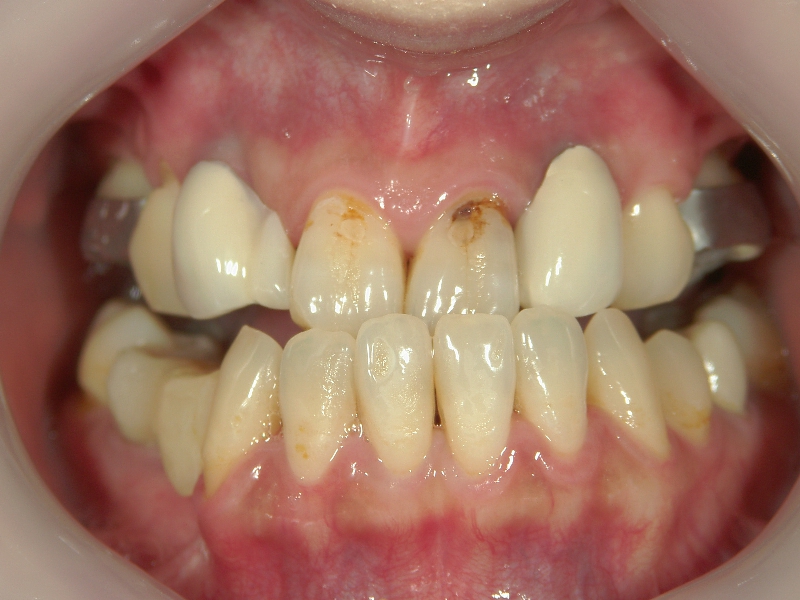

上顎に比べ、下顎が著しく後退しています。

上の歯と下の歯を斜めに繋ぐようにツインフォースという装置を装着します。装置の力で、顎が前方へ押し出されてきました。

顎の移動が終了しました。装置を外して、今後はワイヤーを使用して歯列を治します。

矯正治療後の後戻りを想定して、あえて必要量を越えた顎の移動を行います。